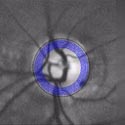

Here are retina images from twins / Ci-dessous deux rétines de jumeaux:

A kind of (circular) barcode is extracted from the pattern of blood vessels, which is stored for further comparison with a new retina image.

Une sorte de code à barres (circulaire) est extrait du réseau vasculaire, qui est stocké afin de permettre plus tard une comparaison avec une nouvelle image de rétine.

First the intensity profile is extracted, then a circular scan is performed to locate blood vessels.

Les lignes de plus fortes intensités sont d'abord extraites, puis un scan circulaire permet d'identifier la localisation des vaisseaux sanguins.